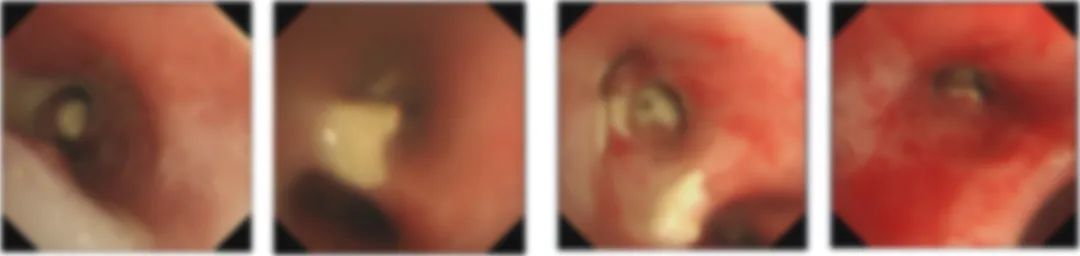

进一步完善气管镜检查提示:主支气管及各级支气管可见多发干酪样坏死;

△气管镜:主气管及双侧支气管多发分布的干酪样坏死及粘膜溃疡